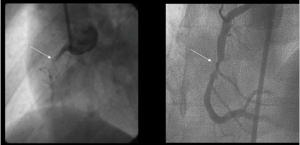

Koroner anjioplasti tıkanmış kalp arterlerini açmak için kullanılan bir prosedürdür. Balon anjiyoplasti, arterin genişlemesine yardımcı olmak için arterin tıkandığı bölüme küçük bir balonun geçici olarak yerleştirilmesi ve şişirilmesi işlemidir. Anjiyoplasti çoğu kez, damarın açık kalmasını sağlamak ve tekrar daralma olasılığını azaltmak için stent olarak adlandırılan küçük bir tüpün sürekli yerleştirilmesi ile birleştirilir. Bazı stentler arteri … Okumaya devam et KORONER ANJİYOPLASTİ VE STENT NEDİR, NASIL YAPILIR?